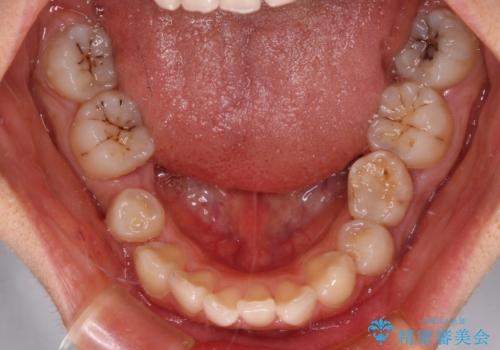

欠損や残存乳歯、深い咬み合わせ ワイヤー矯正で咬合改善

- 後続永久歯の欠損によるスペースと残存乳歯、深い咬み合わせを気にして来院された患者様です。

乳歯を残し、欠損部位のスペースを適正な幅に拡大し、インプラント補綴治療により歯列を整える治療も考えられましたが、ご本人から飛び出している前歯をどうしても引っ込めたいとの要望があったため、残存乳歯ならびに上顎左右第二小臼歯を抜歯して、歯列を整えることとしました。

上下臼歯の咬み合わせ改善には補助装置を、深い咬み合わせ改善にはユーティリティーアーチを活用し、ワイヤー装置にて矯正治療を行うこととしました。